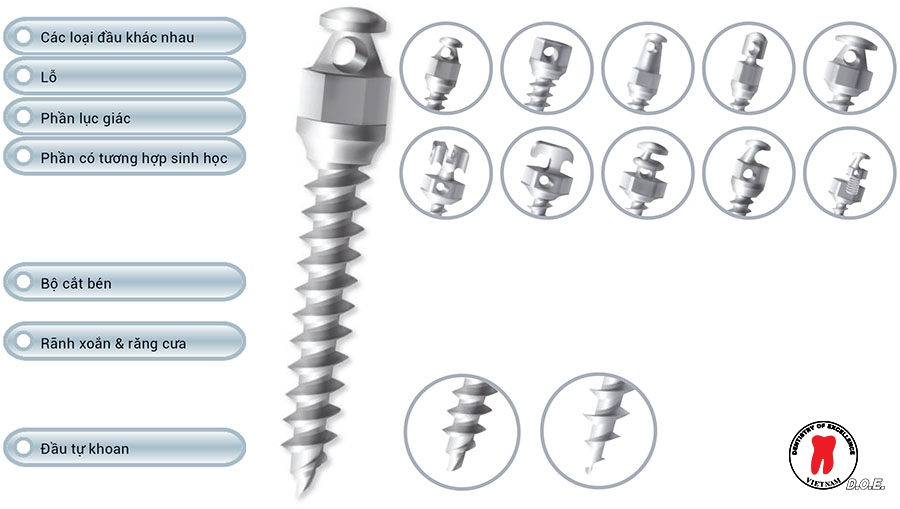

Thiết kế đa dạng đầu – linh hoạt trong nhiều cơ học chỉnh nha

Một trong những ưu điểm nổi bật của minivis Dentos là sự đa dạng trong thiết kế đầu vis. Các dạng đầu vis khác nhau giúp bác sĩ dễ dàng lựa chọn phù hợp với từng kỹ thuật chỉnh nha.

Thiết kế này cho phép gắn dây cung, lò xo, thun liên hàm hoặc các khí cụ chỉnh nha khác một cách linh hoạt. Nhờ vậy, minivis Dentos có thể được sử dụng trong nhiều cơ học chỉnh nha khác nhau, từ các ca điều trị đơn giản đến những trường hợp phức tạp.

Mũi vis sắc bén – hỗ trợ đặt vis dễ dàng

Một yếu tố quan trọng khi sử dụng minivis là khả năng xuyên xương ổn định và ít sang chấn. Minivis Dentos được thiết kế với mũi khoan sắc bén, giúp quá trình đặt vis diễn ra thuận lợi hơn.

Thiết kế này giúp vis xâm nhập xương dễ dàng và ổn định, đồng thời giảm lực cần thiết khi đặt vis. Điều này không chỉ hỗ trợ bác sĩ trong thao tác lâm sàng mà còn giúp giảm cảm giác khó chịu cho bệnh nhân.

Ngoài ra, thiết kế ren vis cũng được tối ưu để tăng độ ổn định ban đầu, yếu tố quan trọng giúp vis hoạt động hiệu quả trong quá trình chỉnh nha.

Khả năng tương thích sinh học cao

Minivis Dentos được sản xuất từ vật liệu titan y khoa (Ti6Ai4Va) , loại vật liệu được sử dụng rộng rãi trong nha khoa nhờ khả năng tương thích sinh học cao và độ bền tốt.